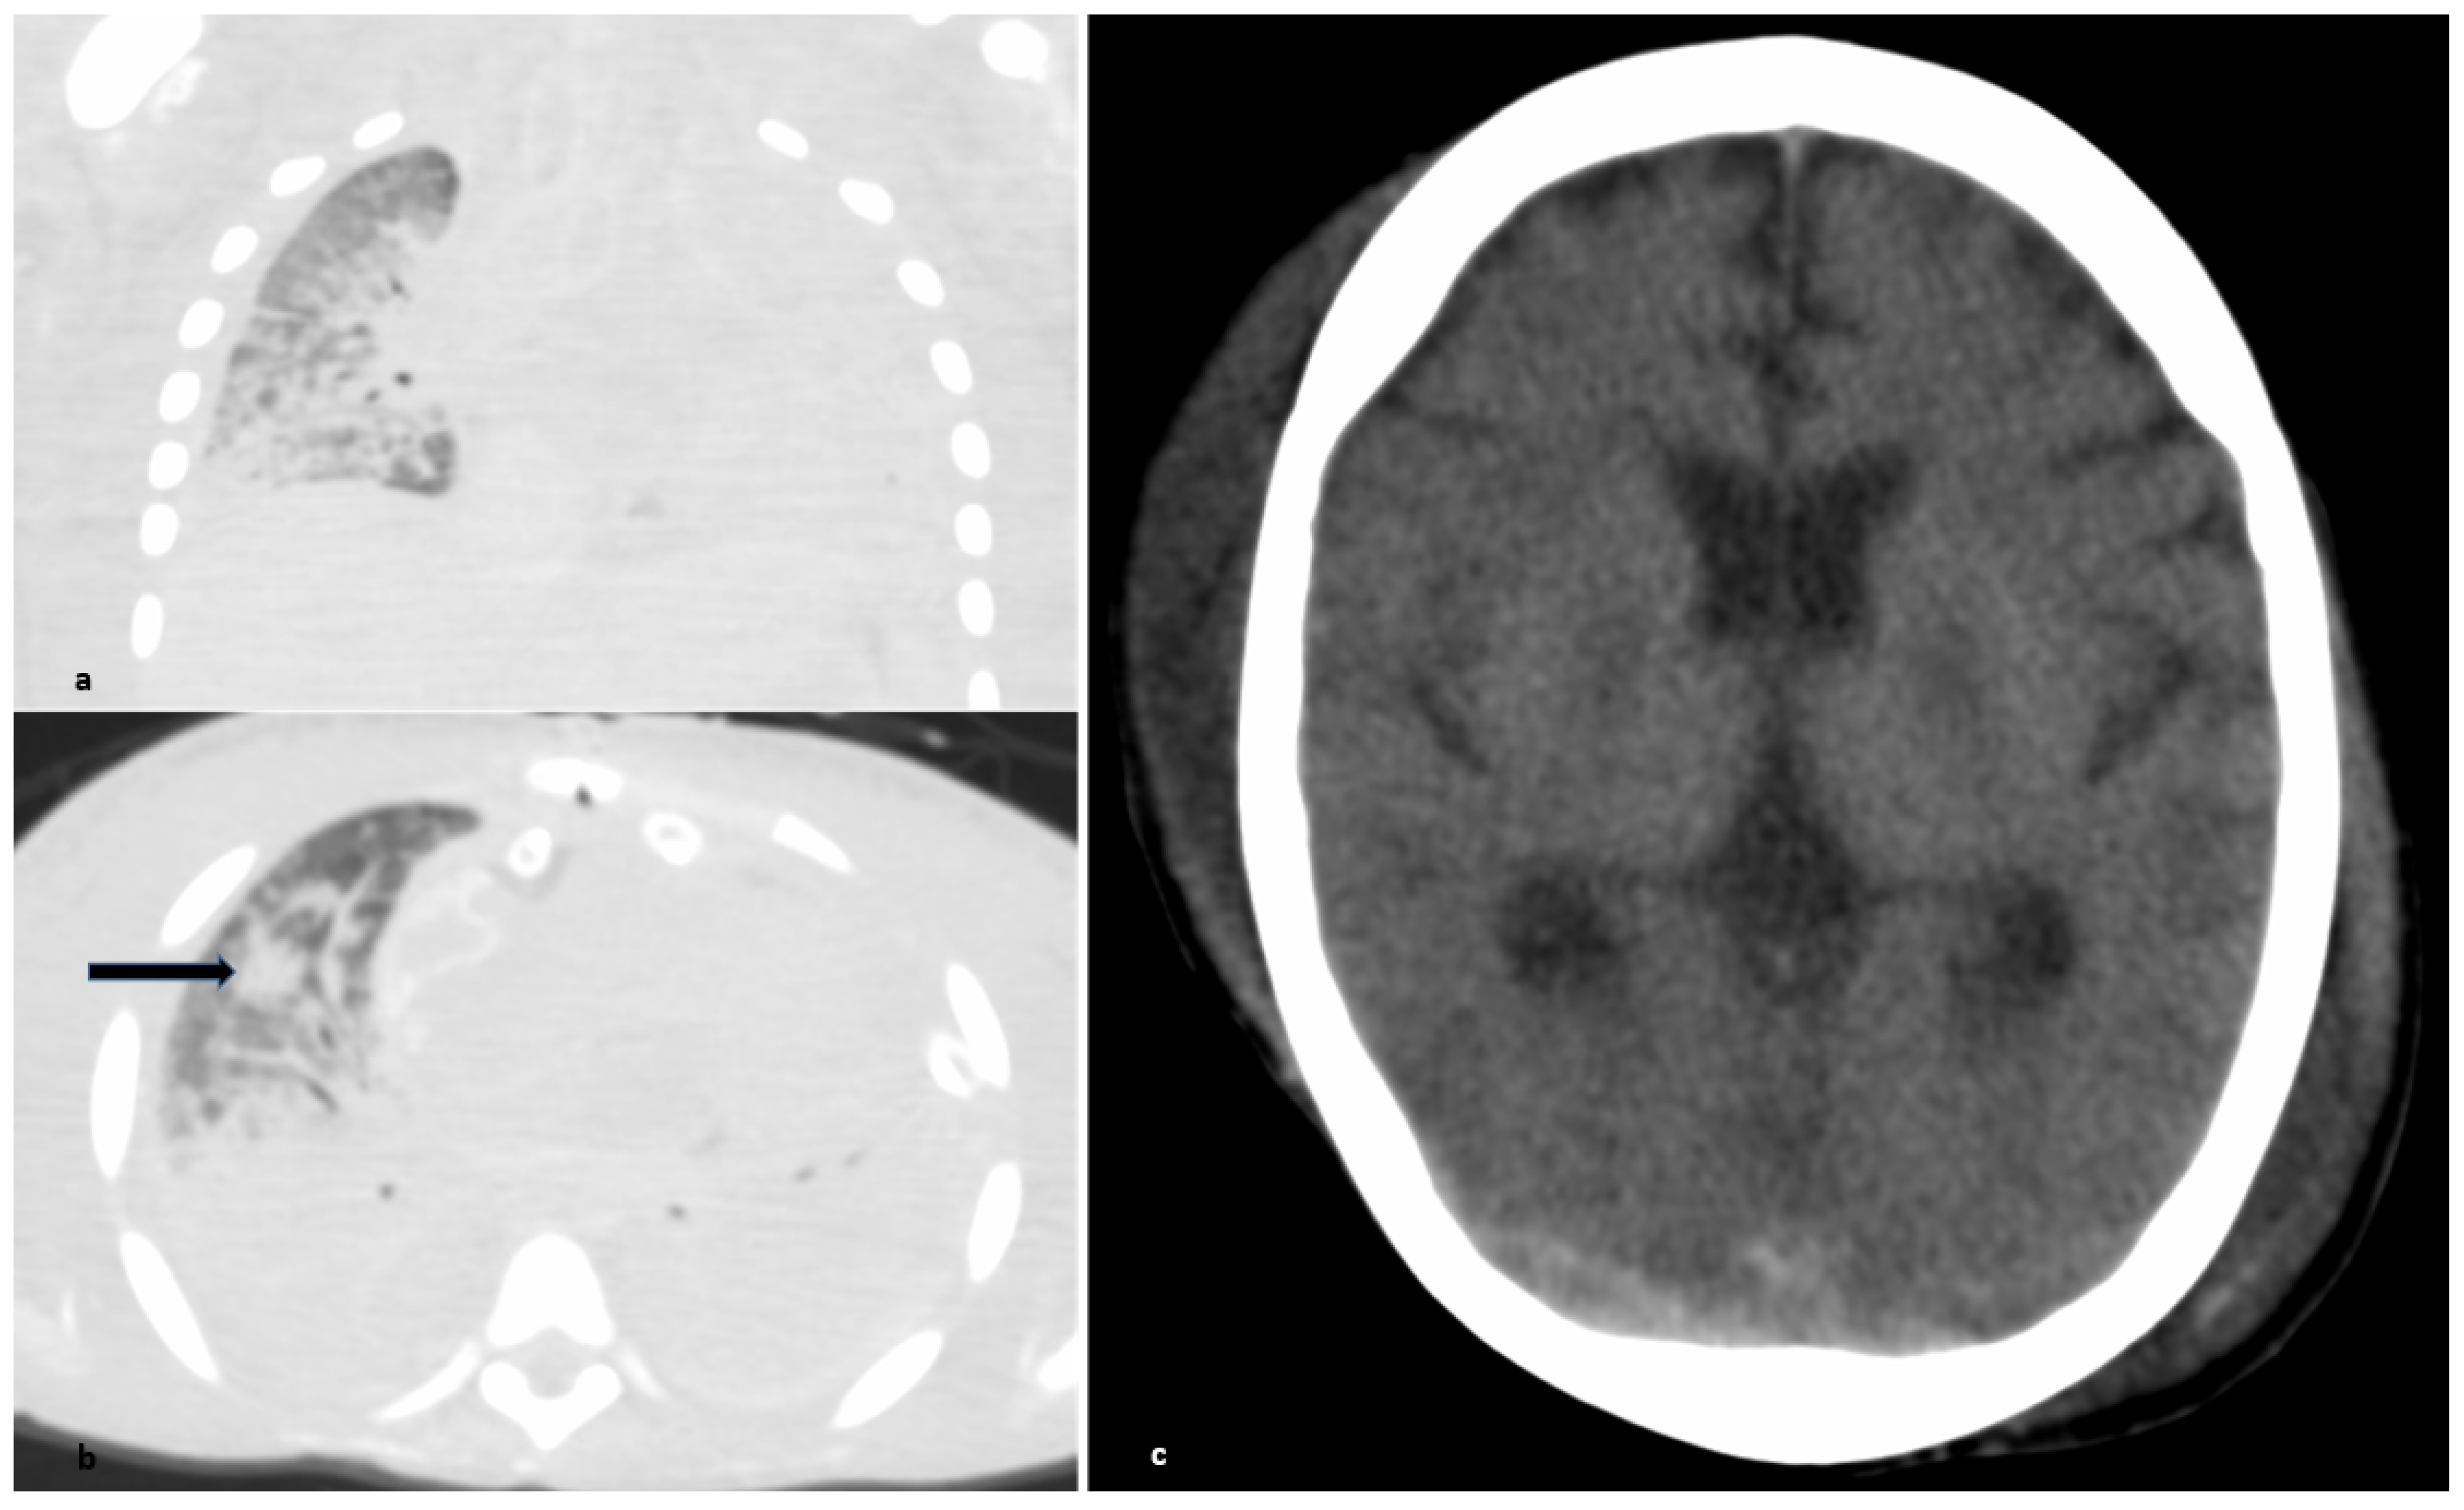

2.1. Respiratory and Cardiovascular System

3. Discussion

- Caturegli, G.; Cho, S.M.; White, B.; Chen, L.L. Acute Brain Injury in Infant Venoarterial Extracorporeal Membrane Oxygenation: An Autopsy Study. Pediatric Crit. Care Med. 2021, 22, 297–302. [Google Scholar] [CrossRef] [PubMed]

- Kniep, I.; Lutter, M.; Ron, A.; Edler, C.; Püschel, K.; Ittrich, H.; Heller, M.; Heinemann, A. Postmortale Bildgebung der Lunge bei COVID-19-Todesfällen [Postmortem imaging of the lung in cases of COVID-19 deaths]. Radiologe 2020, 60, 927–933. [Google Scholar] [CrossRef]